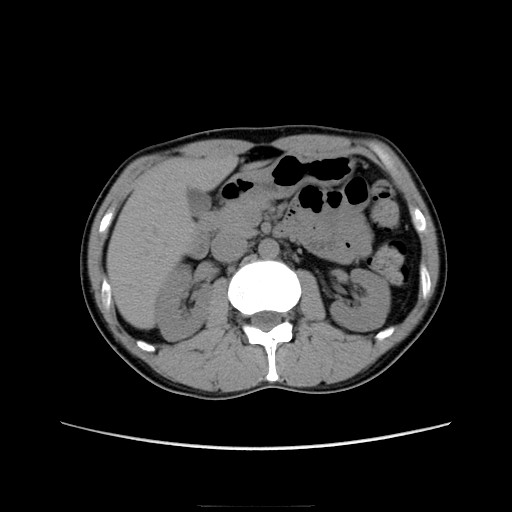

先週の検査結果を聞いてきた。

CT画像、腫瘍マーカー共に問題なし。

ではその「3cm」をCTで確認しましょうw。

おへそのあたりの部分です。